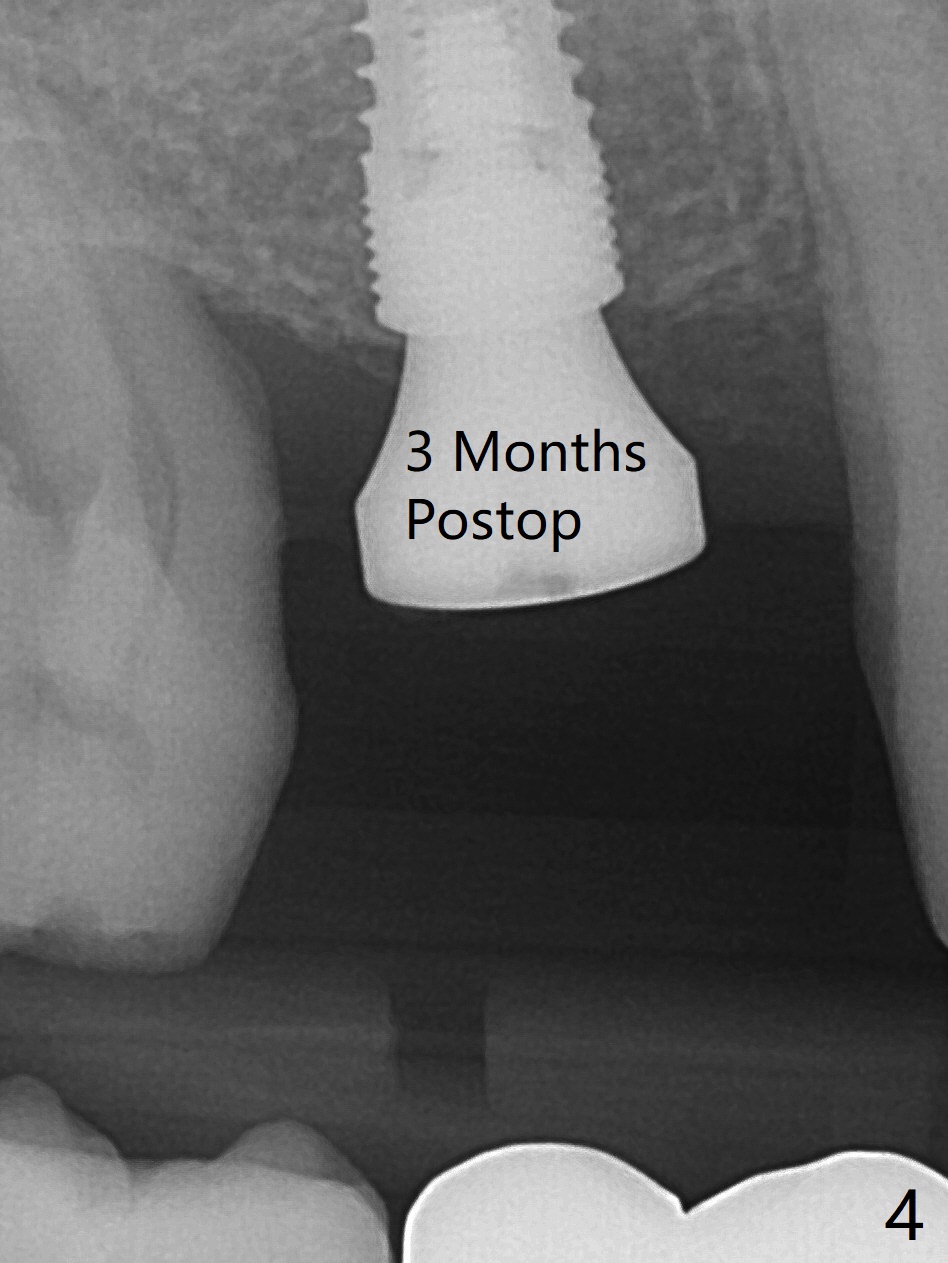

After osteotomy at #3 with IS guide, a 4.5x8 mm SM implant has to be placed free hand because of mismatch of the SM implant and IS guided fixture driver. With minor adjustment, the implant is placed subcrestal to reduce chance of future periimplantitis (Fig.1,2). There is oozing in the osteotomy, which seems to stop when the implant and healing abutment are placed. The patient returns with oozing next day. The temporary FPD is removed. The oozing is coming from the area around the healing abutment. Gauze pressure appears to be effective. After application of periodontal dressing (Fig.3 D) around the healing abutment, the temporary FPD is inserted (T). Hemostasis occurs. Fig.3 is taken 7 days postop. The implant remains subcrestal 3 month postop (Fig.4). A 5.8x7(3) mm cemented abutment is placed for a separate provisional.